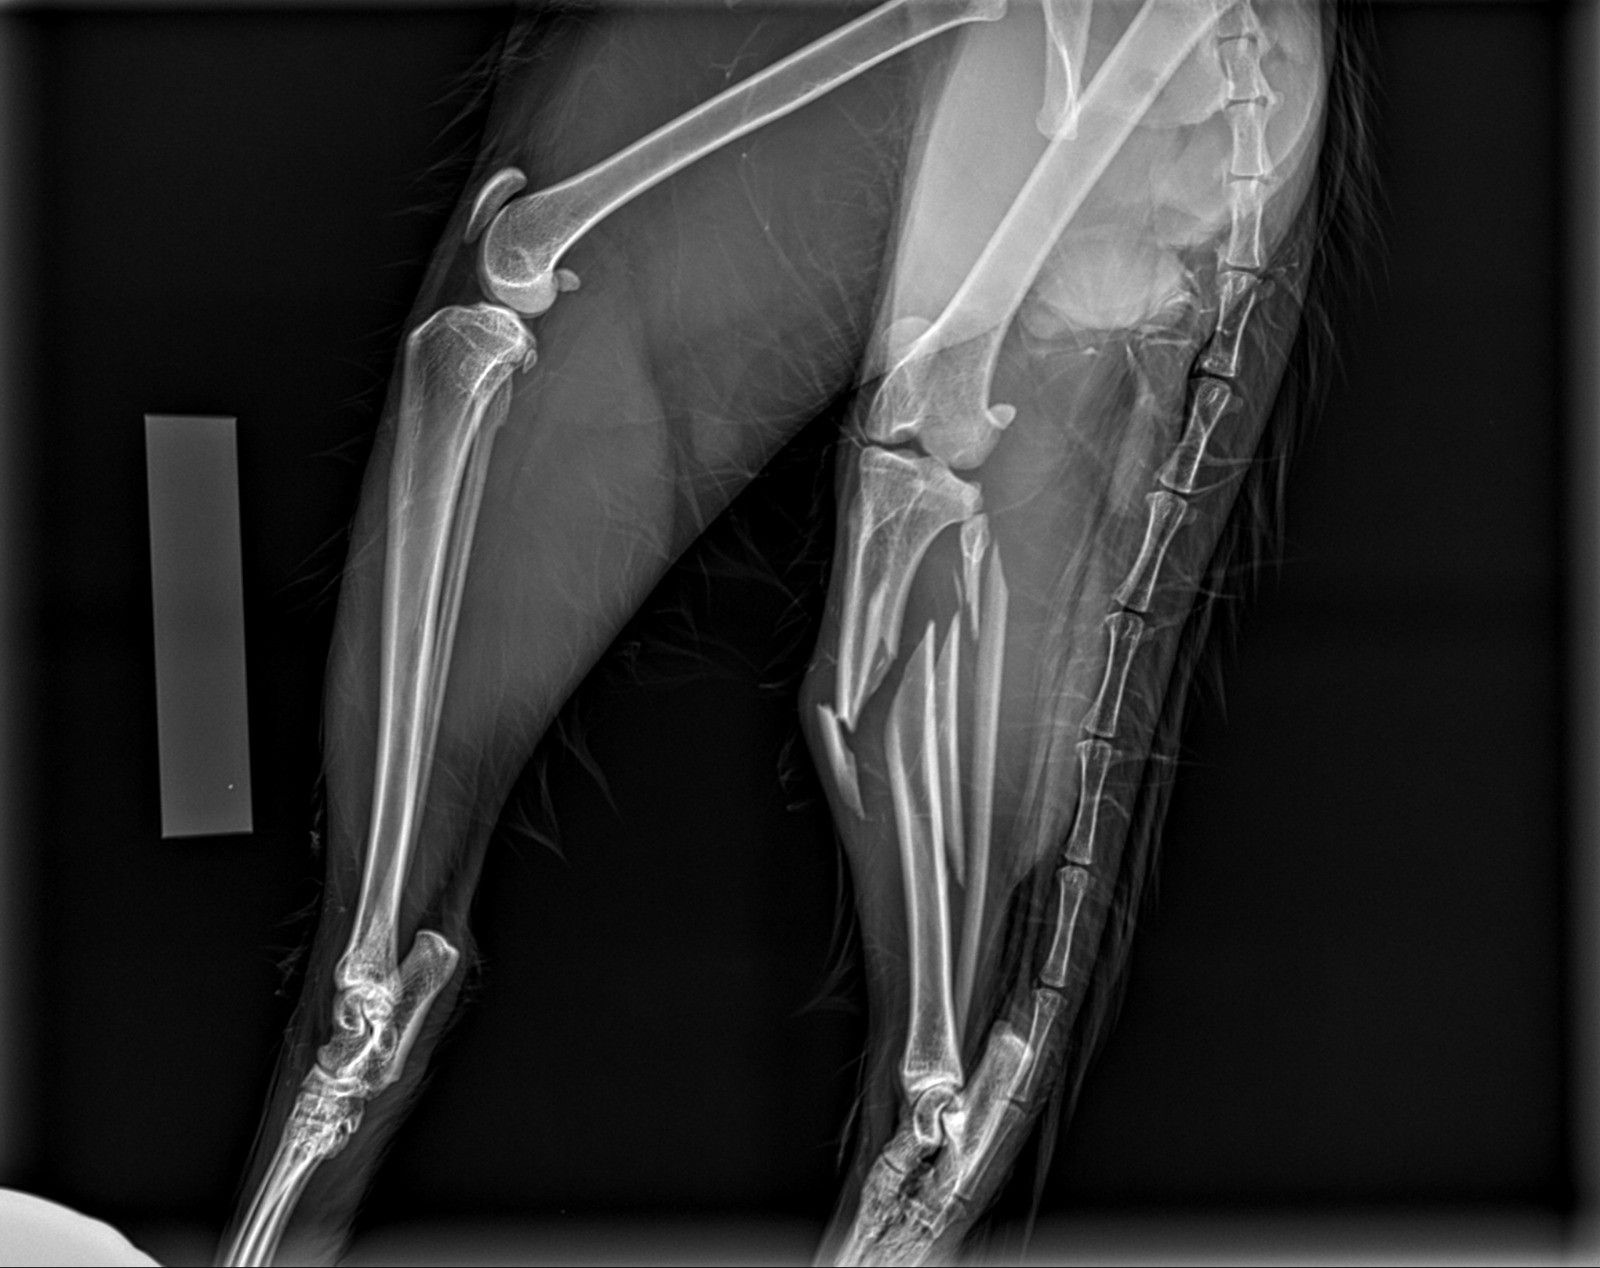

Per offrire cure sempre più efficaci e sicure, la struttura si avvale di tecnologie di ultima generazione. Un nuovo apparecchio radiografico digitale diretto consente diagnosi rapide e dettagliate, migliorando l’accuratezza delle valutazioni cliniche. Inoltre, la collaborazione con un chirurgo esperto e l’impiego di strumentazione chirurgica all’avanguardia permettono di eseguire interventi con maggiore precisione, sicurezza e rapidità. Tra questi, la sterilizzazione e altre procedure chirurgiche risultano notevolmente agevolate, garantendo il massimo benessere per il paziente e un recupero più rapido.